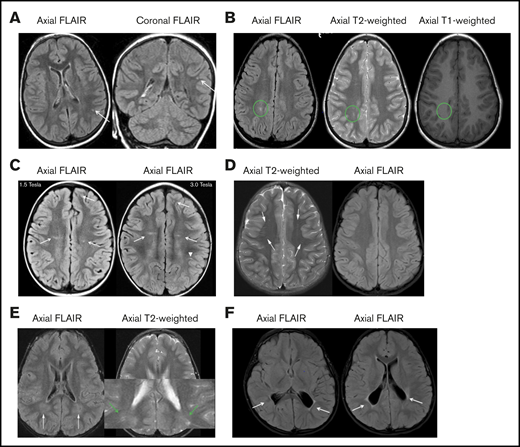

To obtain additional evidence that hydroxyurea decreases TCD measurements, the panel reviewed 10 studies in children with HbSS or HbSβ0 thalassemia who had TCD measurements at baseline and several months after starting hydroxyurea therapy (Figure 4). The decrease in TCD measurements can occur as early as 3 months after starting hydroxyurea therapy with a sustained impact of hydroxyurea therapy on decreasing TCD measurements for at least 36 months. In a pooled analysis of 10 studies, the average drop in TCD measurement after starting hydroxyurea, 21 cm/s, was a clinically relevant decline (Figure 4).

Pooled analysis of the 10 studies documenting TCD measurement before and after hydroxyurea therapy in children with HbSS or HbSβ0thalassemia. This meta-analysis demonstrates the average drop in TCD measurement after starting hydroxyurea therapy of 21 cm/s (95% confidence interval [CI], 14.8-29.0). The plot also suggests that the decrease in TCD measurements can be seen as early as 3 months after the start of hydroxyurea therapy with a sustained impact of hydroxyurea therapy on decreasing TCD measurements for at least 36 months. The analysis is updated from a previous one by DeBaun and Kirkham,58 plus additional references.51-57,59,60,165 ♦ represents the pooled estimate from a random-effect model, the edges of the diamonds represent the 95% CI; ▪ represents individual studies. MTD, maximum tolerated dose.